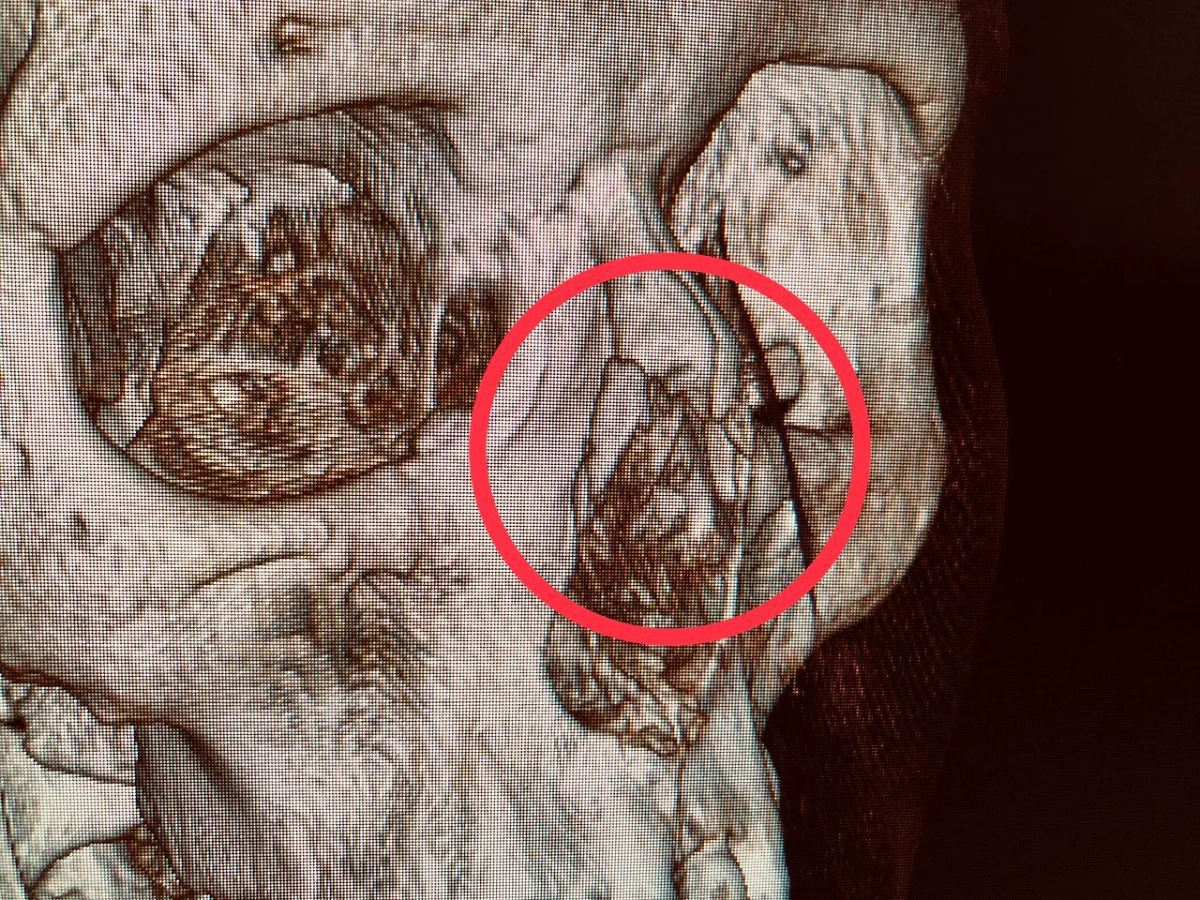

Телефон сломал нос. Фото © Министерство здравоохранения Московской области

В Видновской больнице помогли 24-летней девушке с травмой носа. Пострадавшая уснула, пролистывая ленту новостей в телефоне. Гаджет выскользнул из её рук и упал на переносицу. В результате девушка получила перелом костей носа со смещением отломков. Медики вправили смещённые отломки скелета носа и зафиксировали их в правильном положении. Сейчас девушку уже выписали из больницы, она вернулась к обычной жизни и решила отказаться от использования телефона перед сном.

«Через десять дней после травмы был отмечен прекрасный косметический результат. Орган функционирует нормально», — цитирует врача-оториноларинголога Рауля Тена Министерство здравоохранения Московской области.